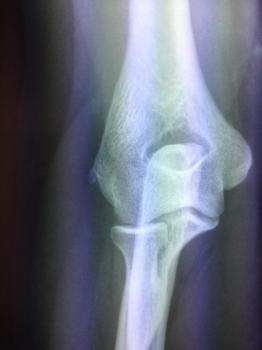

Arthroplastie du coude : prothèse partielle ou totale du coude

Arthrose essentielle idiopathique ou post traumatique, arthrite rhumatoïde ou spondylarthrite ankylosante, fracture sus et inter-condylienne du coude chez la personne âgée et fracture de la .../...

Arthroscopie du coude, douleur du coude

Ostéochondrite, arthrose, synovite rhumatismale, synovite villonodulaire, ostéochondromatose, raideur articulaire, fracture tête radiale et les arthrites septiques

Le coude est une articulation reliant l’extrémité inférieure de .../...